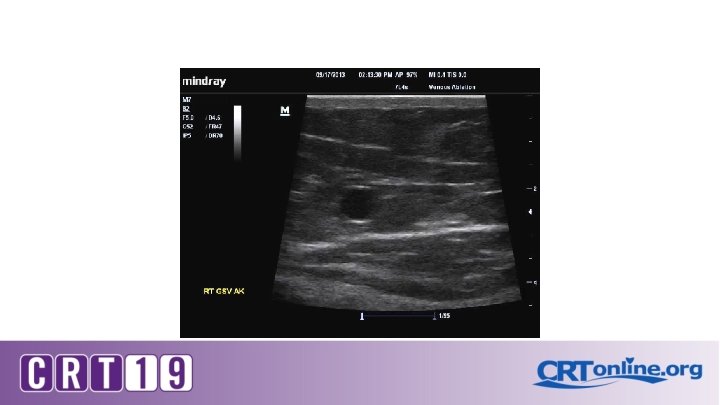

Ultrasound Diagnostic Study � Required in order to determine the source of reflux � Evaluate for venous occlusion or thrombus � Map the course of the incompetent superficial veins

On Ultrasound: Grey scale , color and Doppler Compressibility Phasic flow Augmentation Perforators Reflux and its duration Vein diameters